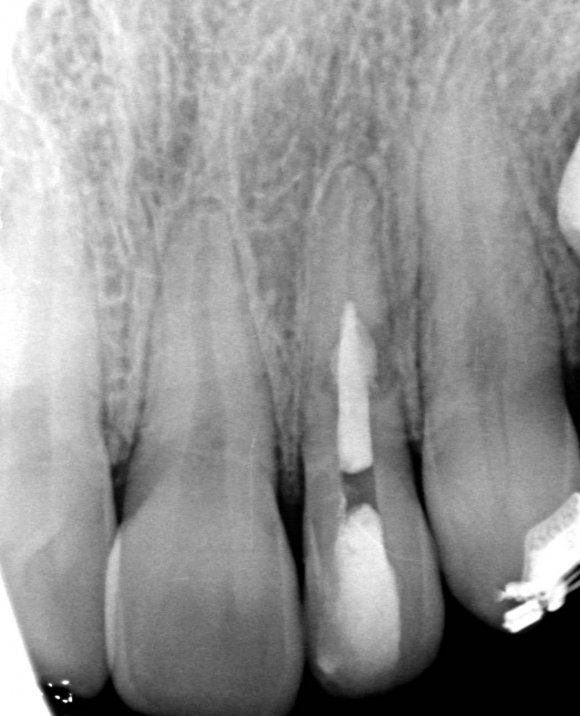

The patient started orthodontic treatment, however, tooth 2.2 was temporarily not included in the orthodontic therapy at the endodontist's request, who was willing to observe it for a year. Furthermore, increased resorption could have been provoked. As of today, the tooth is included in the orthodontic treatment and is being followed up.

In eighteen-month time, the stabilized process is observed, meaning that the diagnosis has been correct and the manual work has been performed without problems. No complaints are observed.